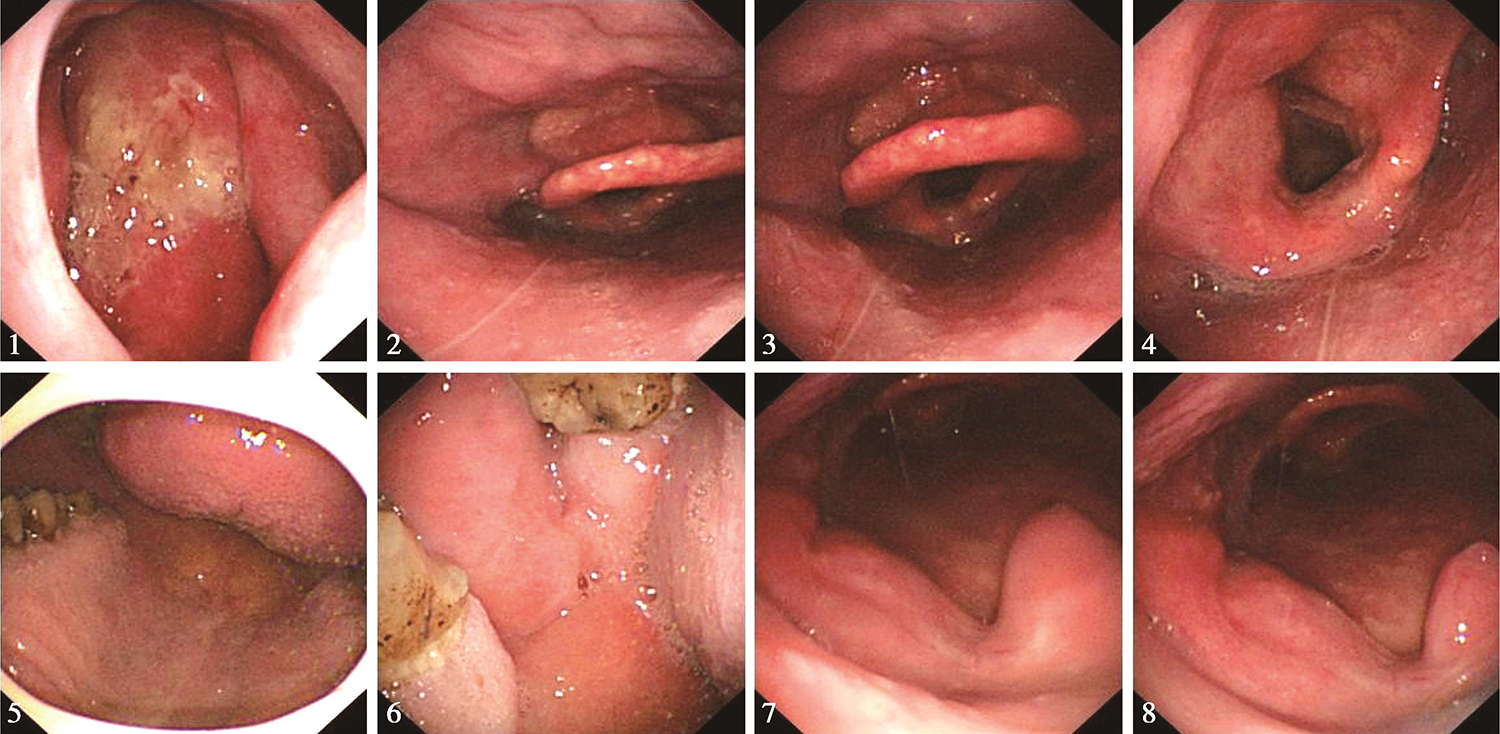

鼻腔进镜顺利。鼻咽部结构完整,黏膜光滑,未见明显异常。经口观察,硬腭基本平整,左侧磨牙后区及左侧软腭和腭舌弓可见溃疡型肿物(活检)(图2),与邻近舌根关系密切,左侧扁桃体处可见溃疡,可疑侵及。口咽右侧壁未见明显异常。舌根部基本平整。下咽及喉部结构完整,未见明显异常。声带活动正常。

图2电子鼻咽喉镜见左侧磨牙后区及左侧软腭和腭舌弓可见溃疡型肿物

口咽左侧壁肿物(性质待病理检查),考虑为癌,侵及左侧磨牙后区。

食管黏膜粗糙且碘染色后可见散在阳性灶(于距门齿约为34cm 3点位处活检1块),距门齿约为36~38cm食管至交界线可见条形糜烂灶(图5),食管胃交界线距门齿约为38cm。贲门、胃底及胃体未见明显异常,胃窦部黏膜充血、水肿、粗糙,幽门充血、水肿。所见十二指肠未见明显异常。

图5电子胃镜见黏膜粗糙且碘染色后可见散在阳性灶;食管至交界线可见条形糜烂灶

内镜诊断:

(1)食管碘染色后阳性灶,建议密切随诊,定期复查。

(2)反流性食管炎,建议对症治疗,治疗后复查。

(2)2016年12月13日电子内镜检查:口咽癌放疗23次复查,鼻腔进镜顺利。鼻咽部黏膜充血,表面平整,可见有分泌物。经口观察,左侧磨牙后区肿物较前消退明显,局部仍显肿胀,不平整。左侧扁桃体区肿物较前消退明显,较前变平,略显隆起(图7)。软腭水肿明显。下咽及喉部未见明显异常。声带活动正常。

内镜诊断:口咽癌放疗中,左侧磨牙后区及左侧扁桃体区肿物较前消退明显,现可见略隆起。

图7电子内镜见口咽左侧壁肿物较前缩小

1)2017年1月11日电子内镜检查:

口咽癌放疗末复查,鼻腔进镜顺利。鼻咽部有分泌物,黏膜略充血,未见明显异常。经口观察,左侧磨牙后区基本变平,略肿胀。左侧扁桃体处肿物似消退,肿瘤已不具体(图8)。舌根部基本平整。下咽及喉部未见明显异常。声带活动正常。

内镜诊断:口咽癌放疗末,左侧磨牙后区和左侧扁桃体处肿物已不具体,基本变平,注意随诊。

图8电子内镜见左侧扁桃体处肿物似消退